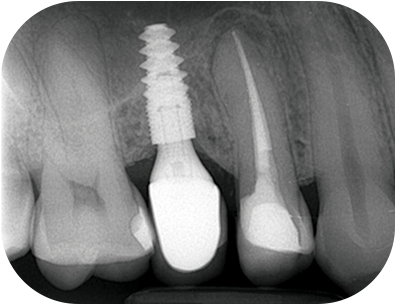

prémolaire, la LIPOE Fig. 02 : la LIPOE est centrée sur la racine

palatine et le canal est clairement

identifiable au CBCT.

prémolaire, la LIPOE Fig. 04 : le canal vestibulaire est totalement oblitéré, sans signe d’infection visible.

prémolaire, radio pré-opératoireFig. 05 : radio pré-opératoire.

prémolaire, radio per-opératoire cone en placeFig. 06 : radio per-opératoire cone en place.